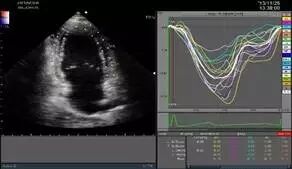

智能眼(EyeballEF)

ARIETTA智能眼技术已实现全实时状态下全自动测量并计算心功能参数,尤其在麻醉、心外科手术、药物实验、心率失常等领域独领风骚。